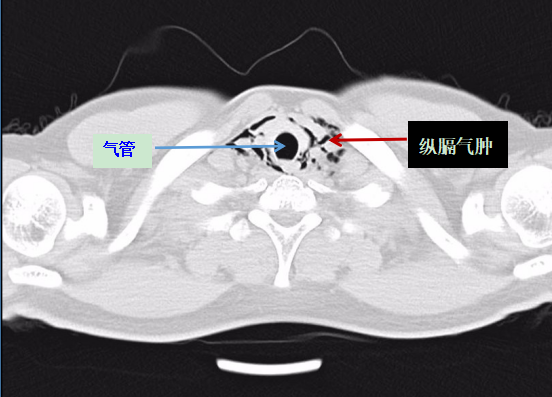

医生表示:根据胸部CT报告,阿岳被诊断为"自发性纵膈气肿",即颈部软组织、纵隔气肿。所幸送医及时,不然后果不堪设想。

阿岳的胸部CT影像